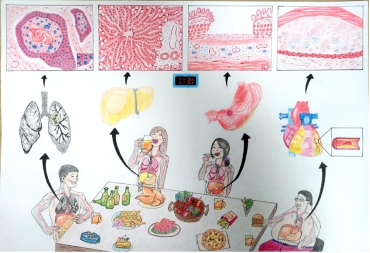

作品名:《不良生活习惯的危害》

作品简介: 吸烟、酗酒、熬夜、暴饮暴食……这是当代绝大多数年轻人的通病。本作品以不良生活习惯对身体健康的危害为切入点,重点描述了其可能对消化、呼吸等系统造成的疾病:肺门中央型鳞癌、脂肪肝、消化性胃溃疡、冠状动脉粥样硬化等。希望通过本作品可以让人们认识到不良生活习惯的危害,呼吁人们要养成良好的生活方式,莫要透支自己的身体!